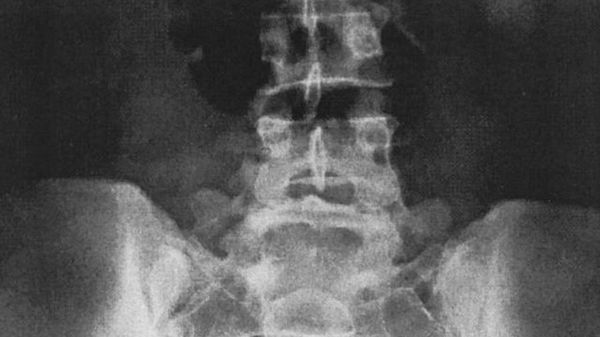

Sui bimbi 4 milioni di radiografie l’anno 4 genitori su 10 non informati dei rischi

Ogni anno in Italia vengono effettuate circa 4 milioni di radiografie su bambini, ma troppo spesso se ne ignorano i rischi. E ben 4 medici su dieci rivelano di non informare i genitori dei possibili danni connessi alla procedura.